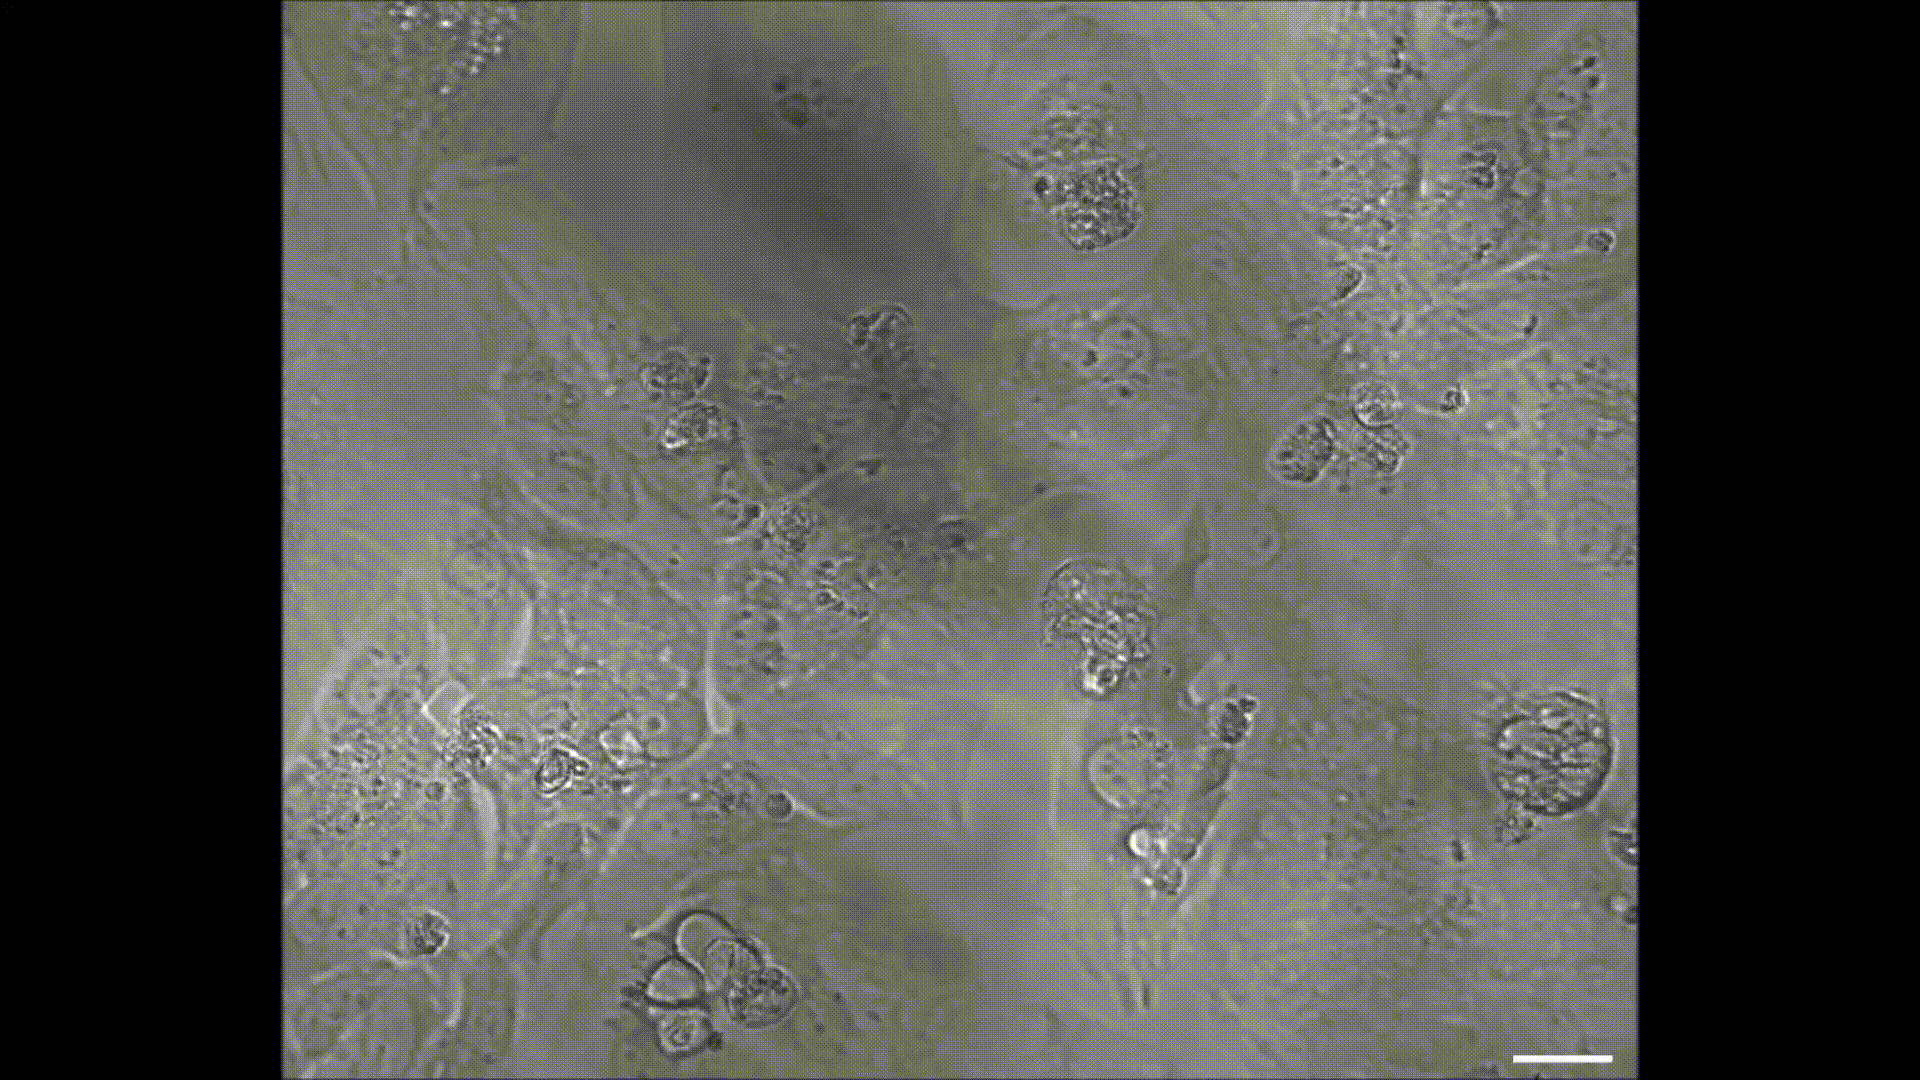

Een groep onderzoekers is erin geslaagd om het gedrag van in het lab gekweekte hartcellen te beïnvloeden met licht.

Een groep wetenschappers van de University of California San Diego School of Medicine heeft namelijk ontdekt dat wanneer je hartcellen kweekt op grafeen je hun gedrag kunt controleren. Door simpelweg de cellen met licht te beschijnen, gaan ze bijvoorbeeld sneller kloppen.

Daarom besloot hij – samen met zijn team – om cellen te kweken op grafeen. Al vrij snel kwamen de wetenschappers erachter dat cellen in het lab veel beter groeien op grafeen dan op andere materialen en zich ook meer gedragen als cellen in het lichaam, wat onderzoek ernaar alleen maar ten goede komt.